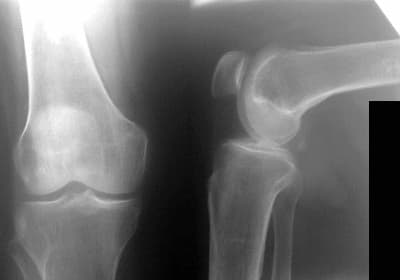

Лобар Хамраева: Салом, юборган расмларимни кўриб чиқинг, илтимос, ҳамма нарса шунчалик қўрқинчлими? Мен нимага тайёрланишим керак?

- Лобар, сизда иккинчи даражали прогрессив артроз бор. Сизга даволаниш тавсия этилади, шундагина жиддий оқибатлардан қочиш мумкин. Хозирча ваҳима ўрин йўқ, клиникамизга ташриф буюринг ва мен сиз учун даволаш режасини ишлаб чиқаман.